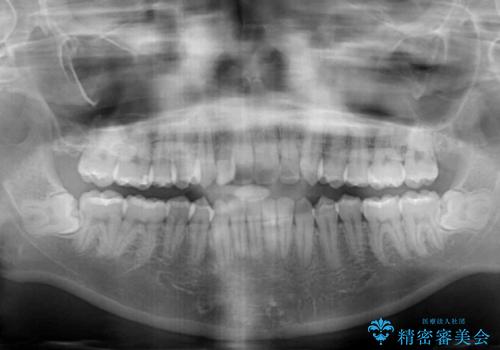

レントゲン写真上では、矯正治療前後で歯根長さに大きな違いはなく、抜歯を回避することができました。

上顎内側に転位している前から2番目の歯は移動が難しく、無理矢理歯根全体を動かそうと設計すると、歯肉退縮・歯髄壊死・歯根吸収といった危険性が増すため、無難なゴールにて治療を終えることとなりました。